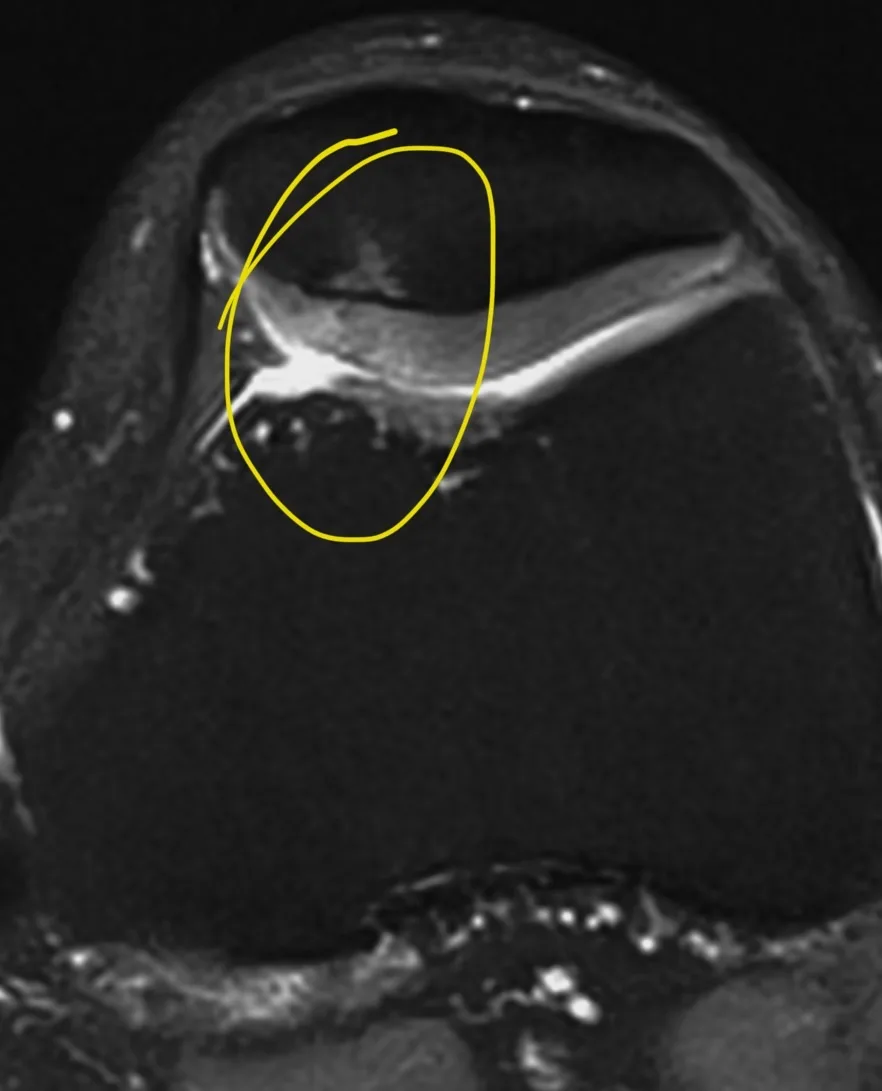

Симметричные, но не полностью, разрушения хрящей надколенников. Сочетание перегрузок с легкой пателло-феморальной дисплазией (а она, чаще всего, двусторонняя), делают свое чёрное дело. Естественно, что правая нога, как опорная, пострадала больше. Справа трещины в хряще глубокие, достигают кортикальной кости, слева пока лишь есть неравномерность структуры хряща. Но с обеих сторон есть реакция губчатой кости, отёк из-за перегрузки.